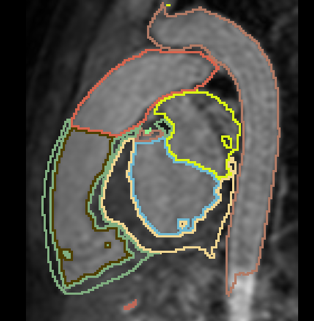

- Aim: segment all cardiac chambers and great vessels from cardiac MRI, for children with congenital heart disease.

- 20 training cases + large anatomical variability - remains a challenge for automatic segmentation.

- Approach: Integrate some interaction from the user, e.g. scribbles or landmarks.

- Already have framework for interactive segmentation. Currently testing using scribbles for aorta segmentation.